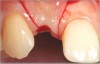

Fig 17. Vertical and horizontal incisions were sutured to attain primary closure.

Figure 17

Fig 18. The final restoration after 4 months.

Figure 18